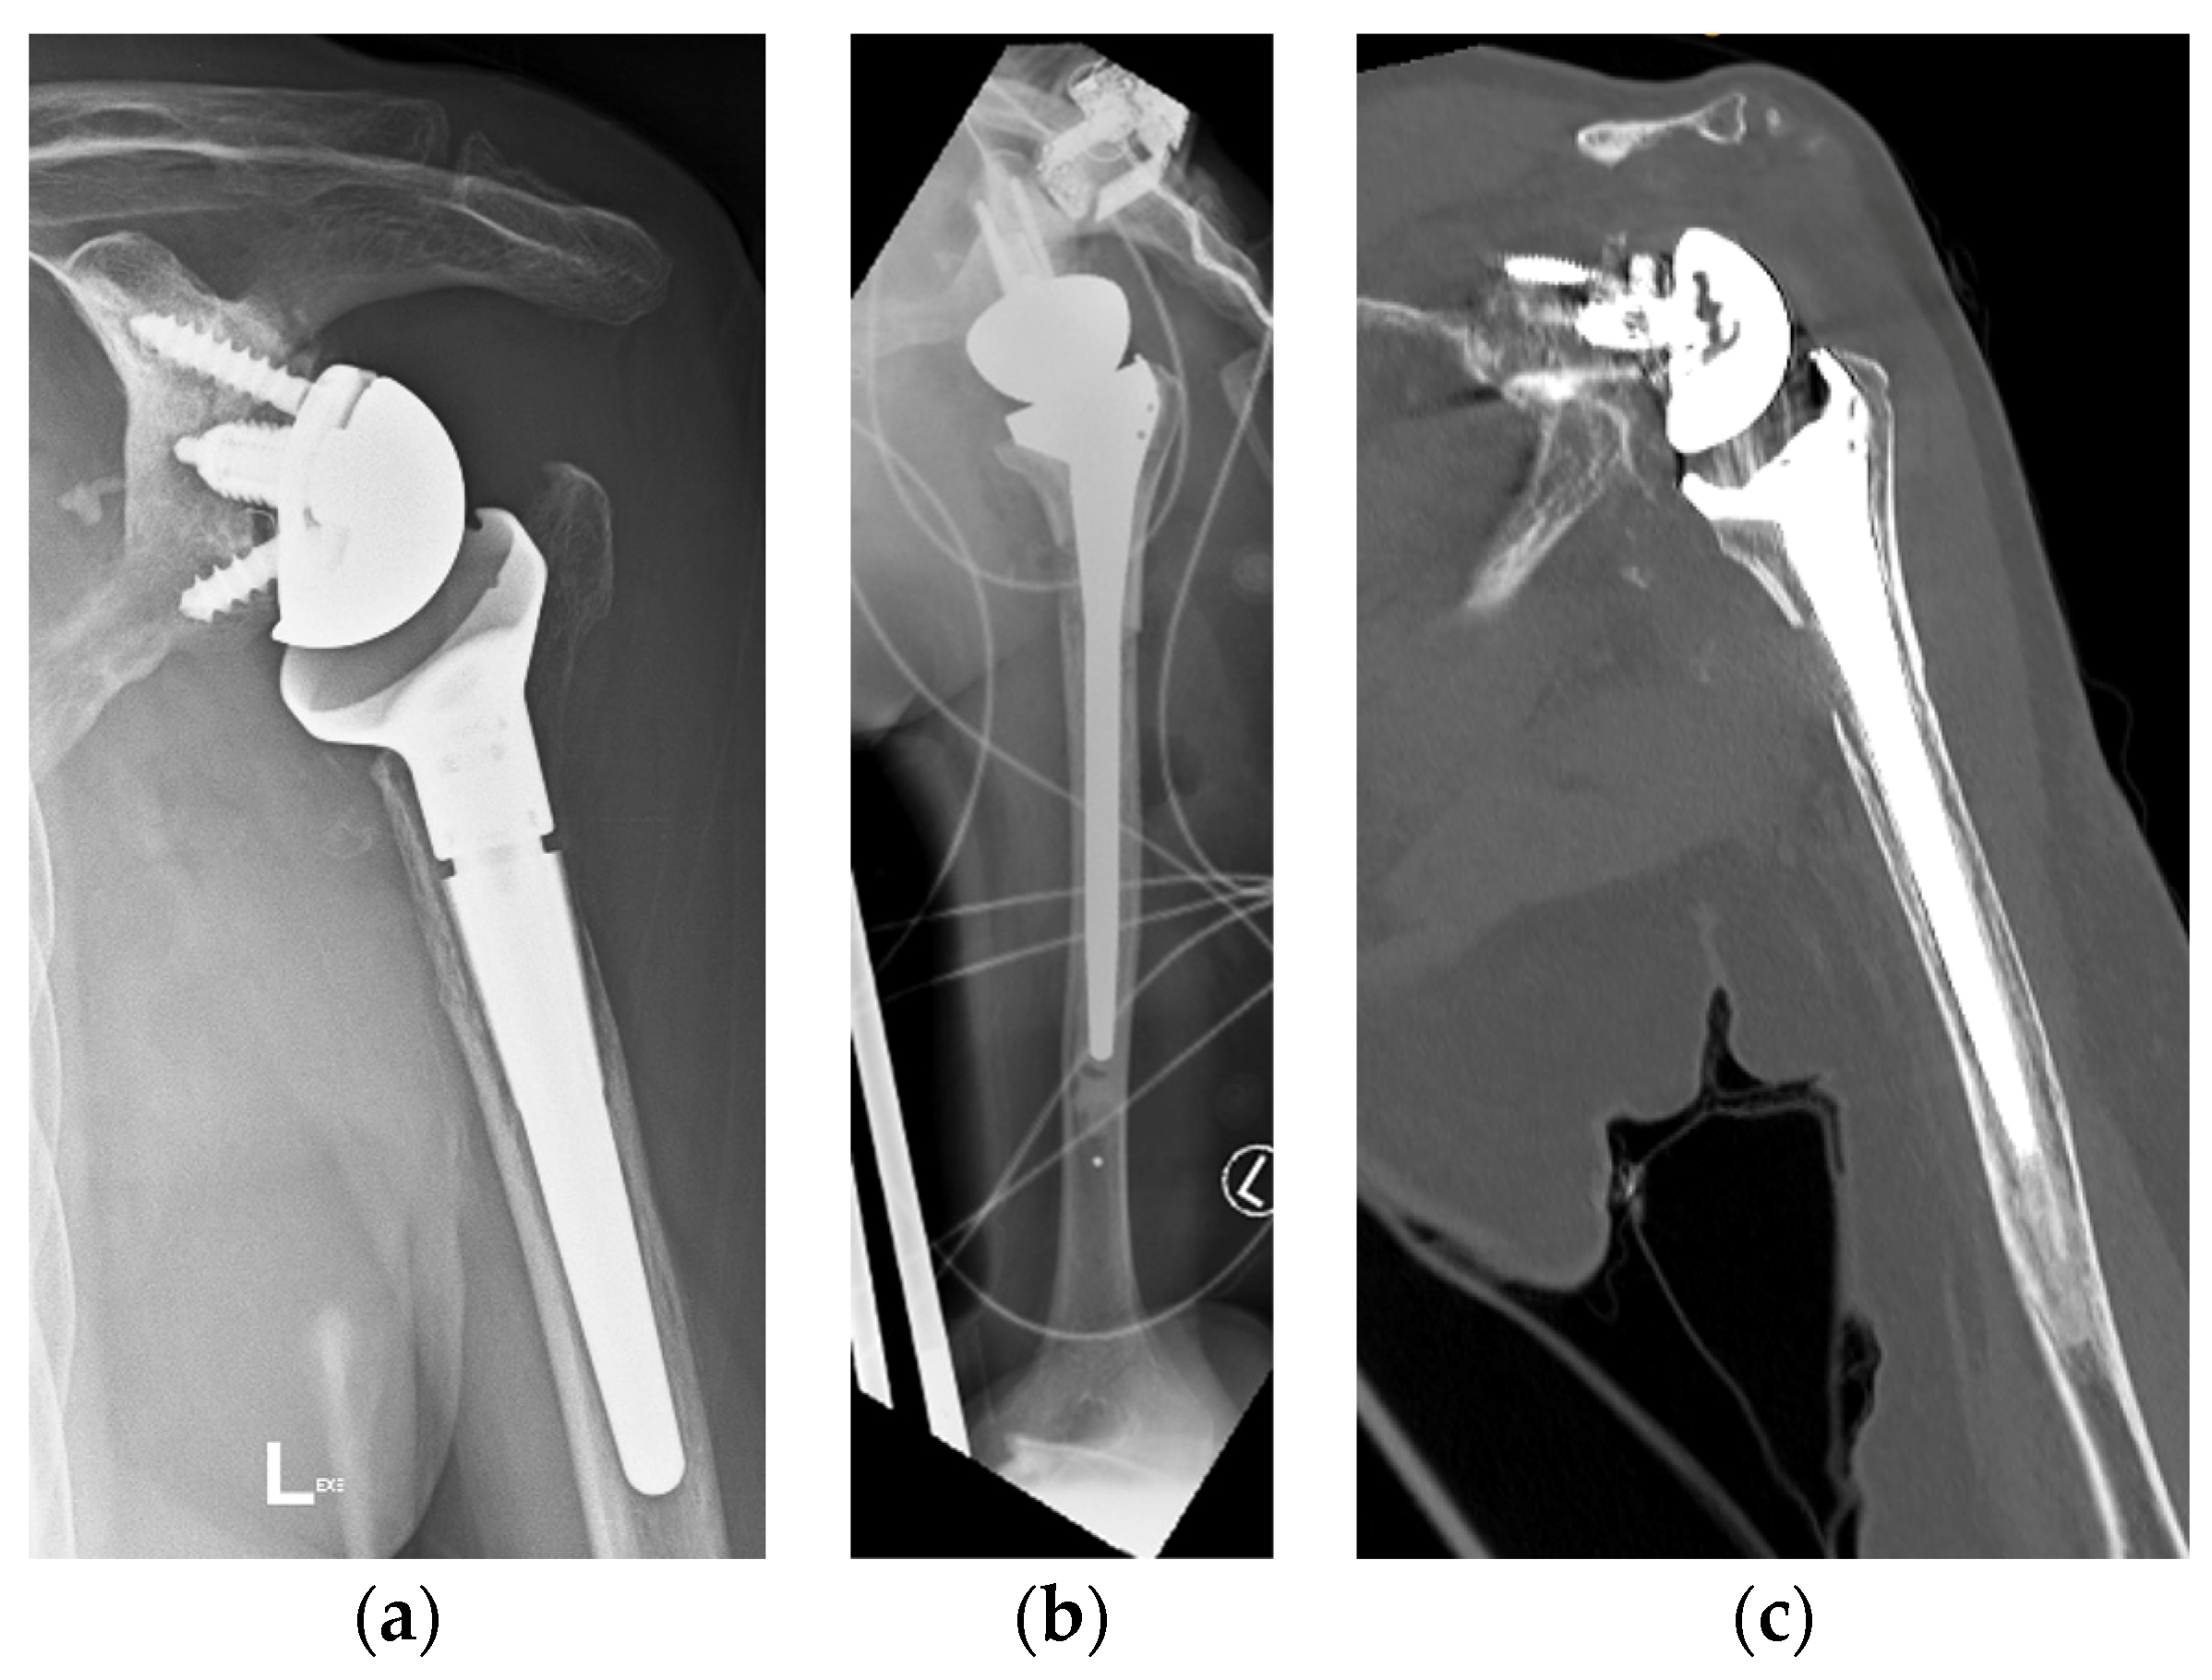

Two patients had repeat CT scans at two years, and one had X-ray at four years, showing complete graft union and no osteolysis (Figure 8). As mentioned, one patient was lost to follow-up, and another refused follow-up imaging.

Figure 8. (a) Preoperative anteroposterior (AP) X-ray showing bone loss on the proximal humerus; (b) immediate postoperative AP X-ray showing reconstruction of the proximal humeral defect using an APC; (c) coronal CT scan showing union of the APC with the native humeral shaft.